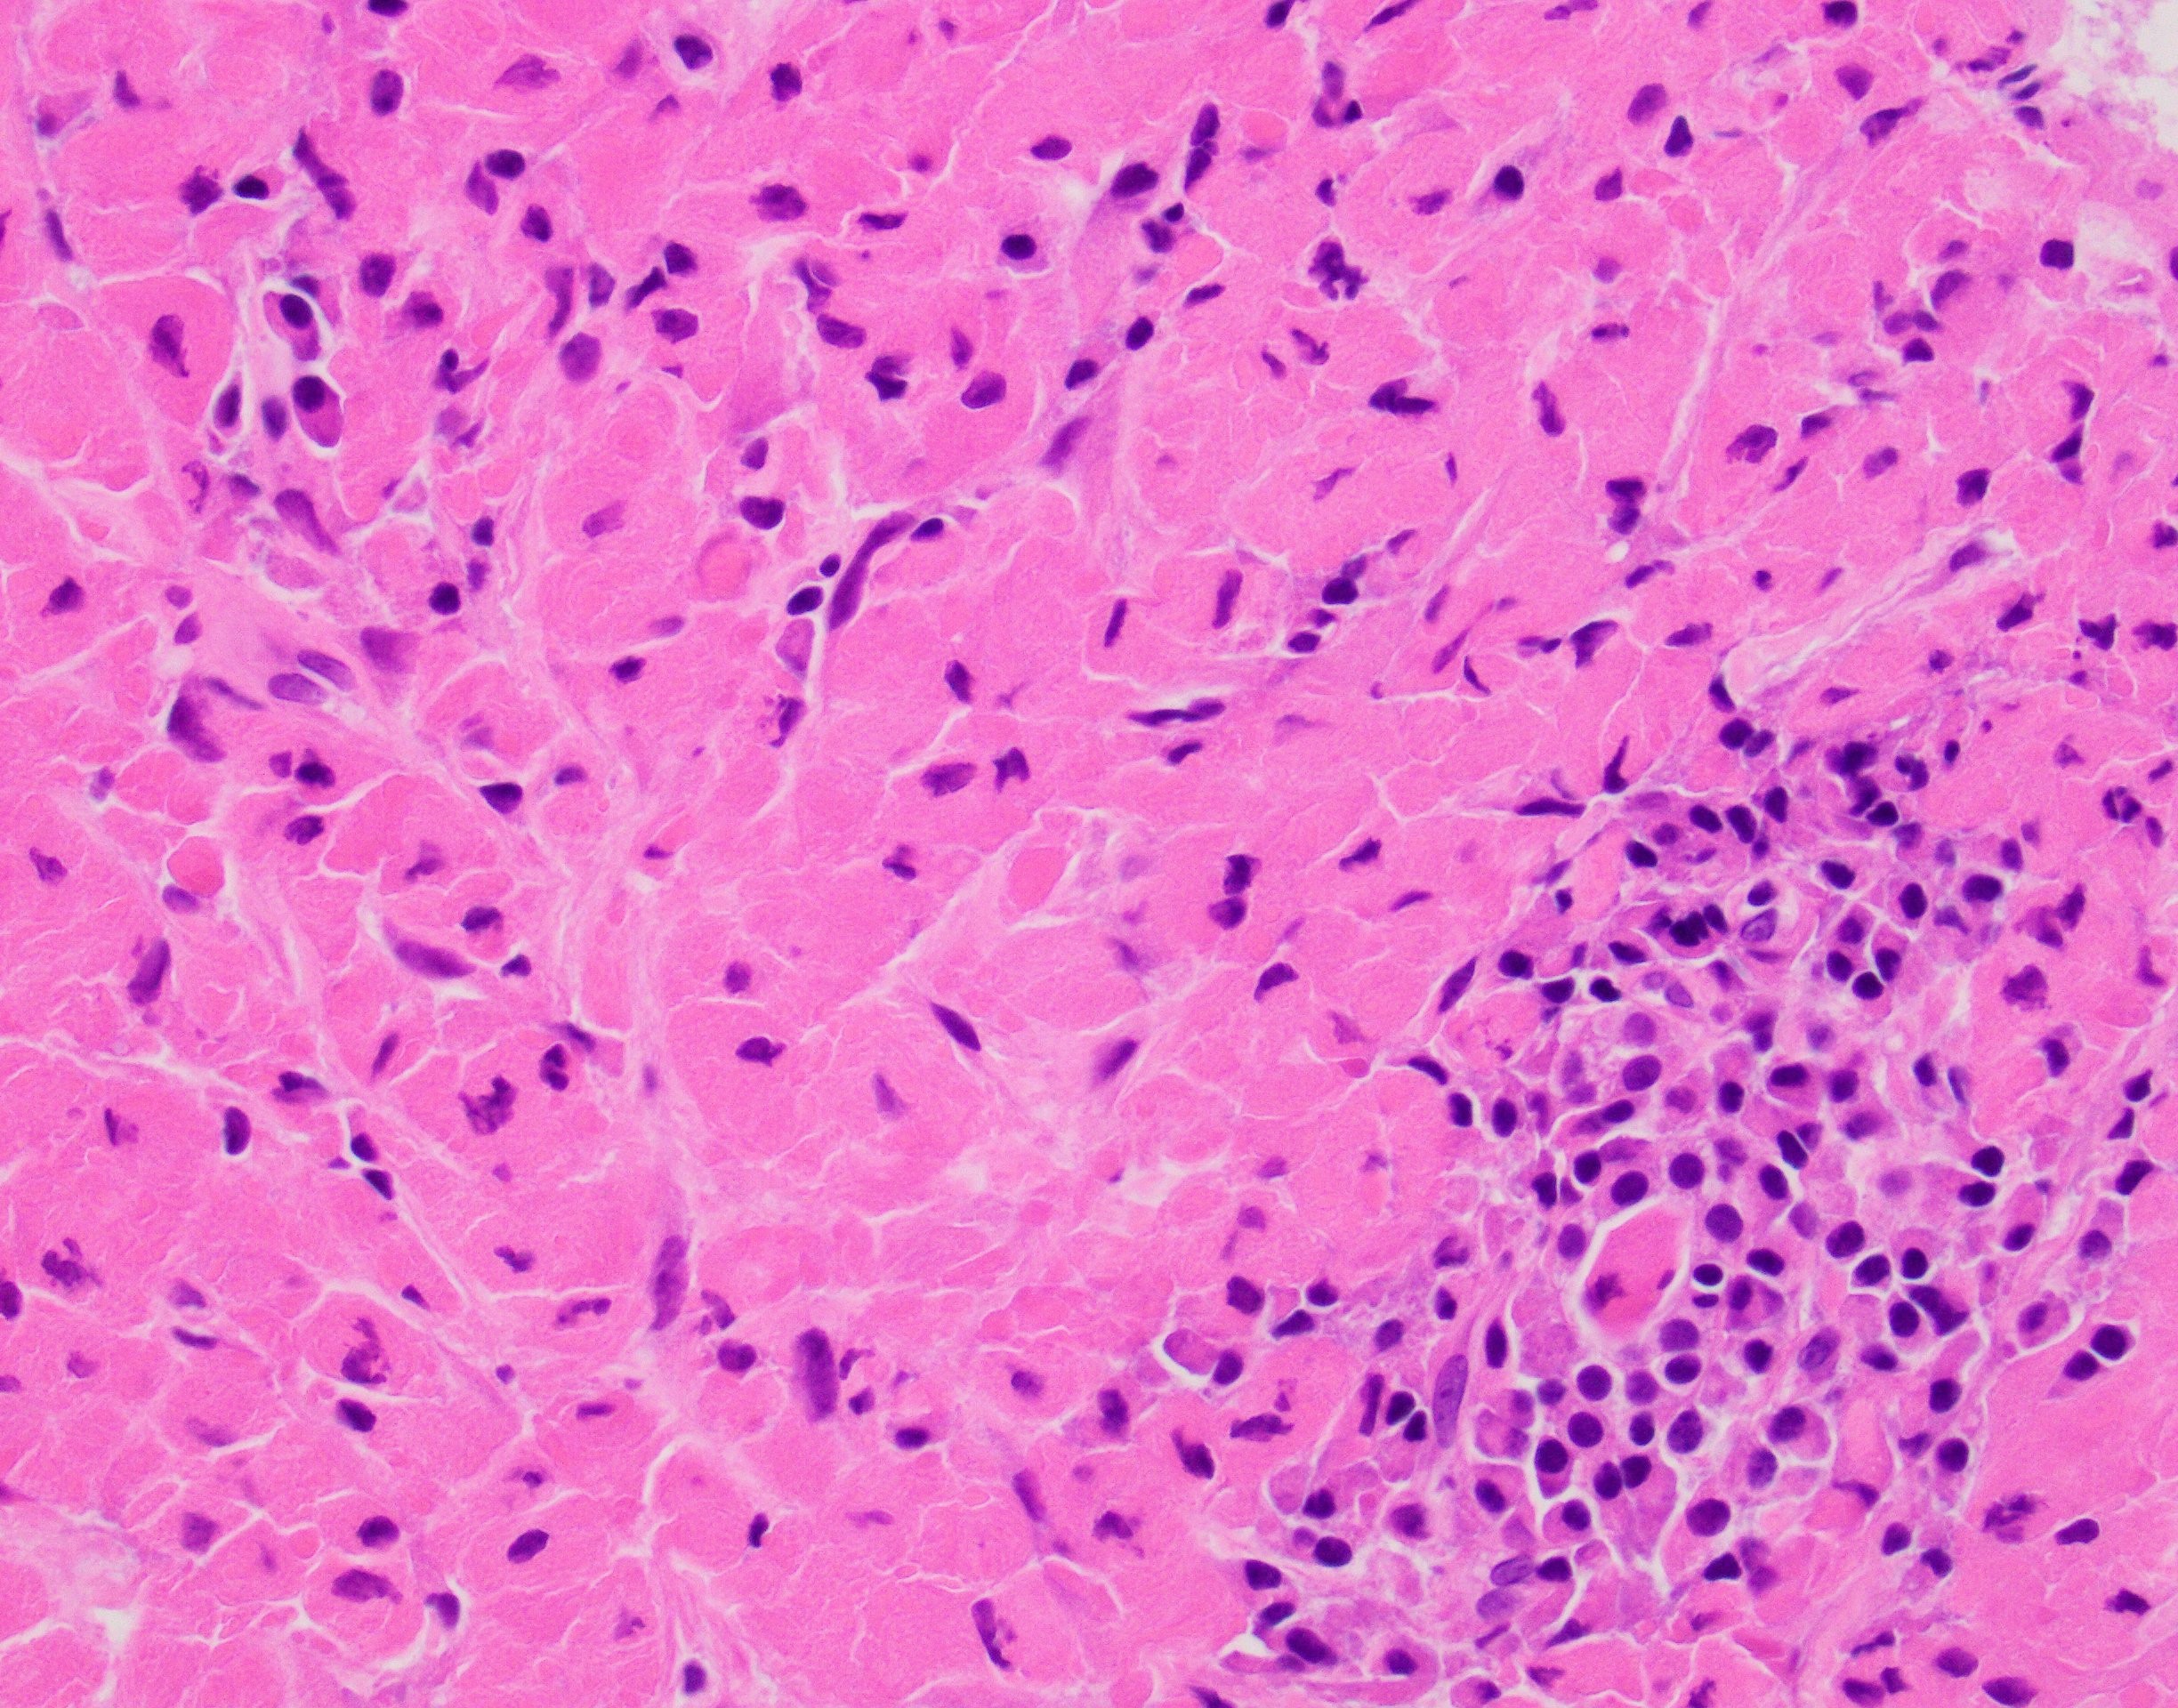

A 66-year-old female with right middle lobe lung lesion (A Sox10 immunostain was negative).

Explantation: H&E sections show a proliferation of histiocytic appearing cells containing brightly eosinophilic crystalloid material that is slightly refringent. In addition there are foci of plasma cells scattered throughout. Immunohistochemical stains for Keratin cocktail, PAX8, Sox10, CD68, CD163 and Kappa/Lambda cocktail were performed with appropriate controls. The cells of interest are strongly immunoreactive for CD68 and CD163 while negative for Keratin cocktail, Sox10 and PAX8. Kappa/Lambda cocktail shows a Kappa light chain restriction in the plasma cells present and the crystalloid material within the histiocytes is also immunoreactive for Kappa light chain.

The overall findings are most consistent with the so-called localized (pleuro) pulmonary crystal-storing histiocytosis a rare disorder that is often related to lymphoproliferative/plasma cell diseases and rarely occurs secondary to long-standing immune-mediated diseases (rheumatoid arthritis) or to chronic use of certain medications (clofazimine).